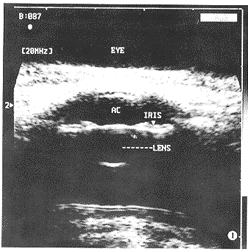

一、正常人眼前节结构的 20.0 MHz超声表现(图1,2)

图1 正常眼前节 20.0 MHz超声图:角膜呈一条弧形高回声,前 房为无回声,虹膜呈短条状高回声,晶状体前后囊膜呈弧形高回声,晶状体内部呈无回声(AC- 前房,IRIS-虹膜,LENS-晶体)

1.角膜:位于眼球的最表面,呈一条弧形向上的高 回声。

4.前房:中央前房由角膜的内表面和晶状体的前界面组成,前房呈无回声。

6.虹膜:可清楚显示鼻侧及颞侧虹膜,呈“短条状”高回声,其前方为前房的后界面一部分,后方为后房的前界面。

9.晶状体:晶状体前囊膜呈弧形高回声,晶状体内呈无回声。

角膜厚度为(0.383±0.031)mm,前房深度为(2.241±0.256)mm,晶 体厚度为(3.533±0.185)mm,虹膜厚度为(0.419±0.044)mm,睫状体厚 度为(1.131±0.094)mm。